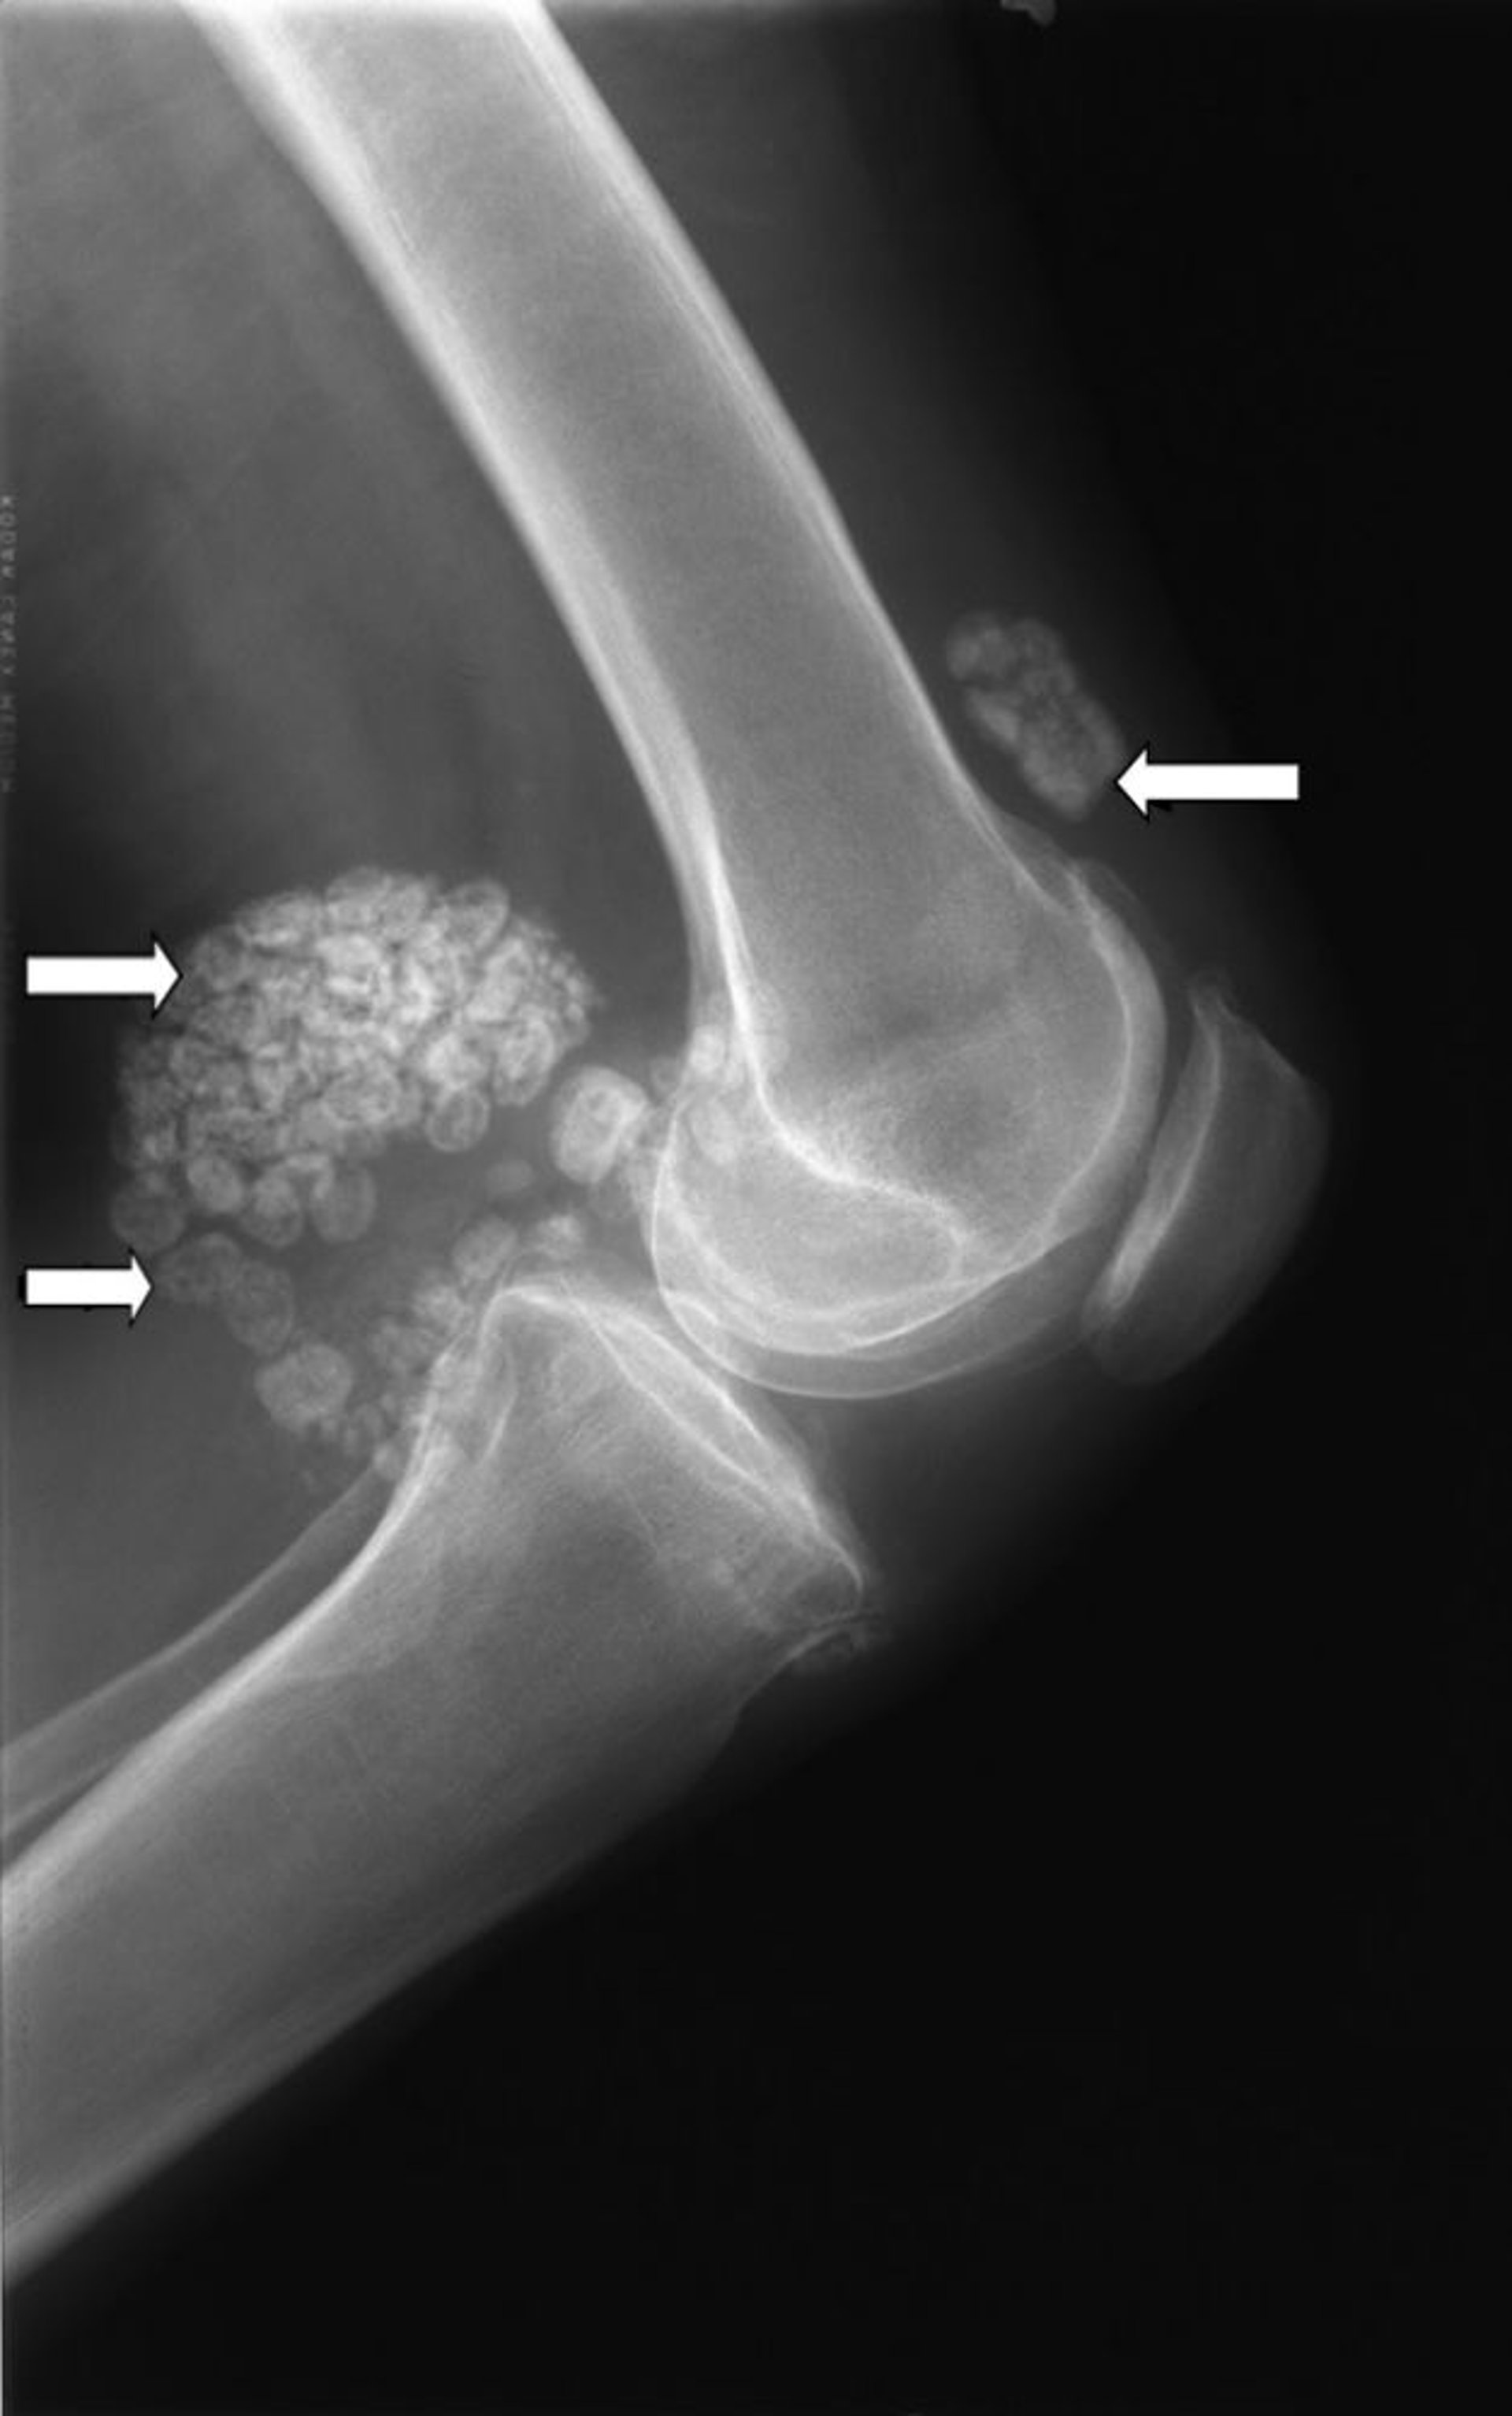

الورم الغضروفي الزليلي

تُظهر هذه الصورة الشعاعية تجمعات متعددة من الغضاريف (اتجاه الأسهم) تُعرف باسم الأورام الغضروفية الزليلية.

جرى استخدام الصورة بعد موافقة أصحابها Michael J.Joyce, MD, and Hakan Ilaslan, MD.